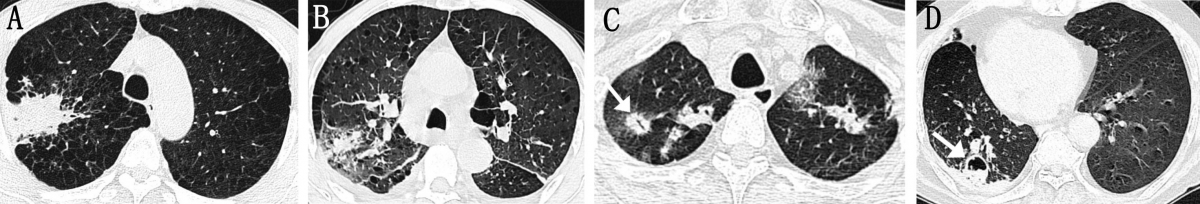

肺炎型COPD-IPA的胸部CT表现

图像来自一位63岁COPD-IPA患者,主要因咳嗽、气短加重伴发热入院,显示右肺上叶肺炎,极易与普通肺炎混淆。

哮喘型COPD-IPA的胸部CT表现

图像来自一位45岁女性COPD-IPA患者,因“反复咳嗽、咳痰3月余,呼吸困难1周”入院。肺功能检查提示中重度阻塞性通气功能障碍。胸部CT(A、B、C)显示多发支气管黏液栓导致气道阻塞及中心性支气管扩张。